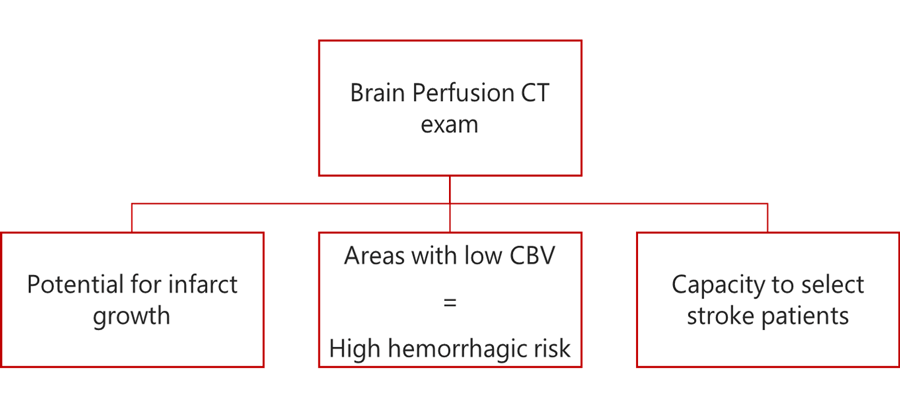

The readily accessible and rapid technique that can help detect any acute ischemic stroke is the Perfusion CT Exa which will evaluate the parenchyma and determine the volume of infarct core and penumbra.

In addition, the Brain Perfusion CT exam will help to reveal 3 things:

- Suggest the potential for infarct growth

- Highlight areas of the brain with low CBV, which will be in high risk for a hemorrhagic transformation following endovascular treatment

- Capacity to select stroke patients likely to benefit from thrombolysis, based on an imaging with no contrast or intracranial hemorrhage